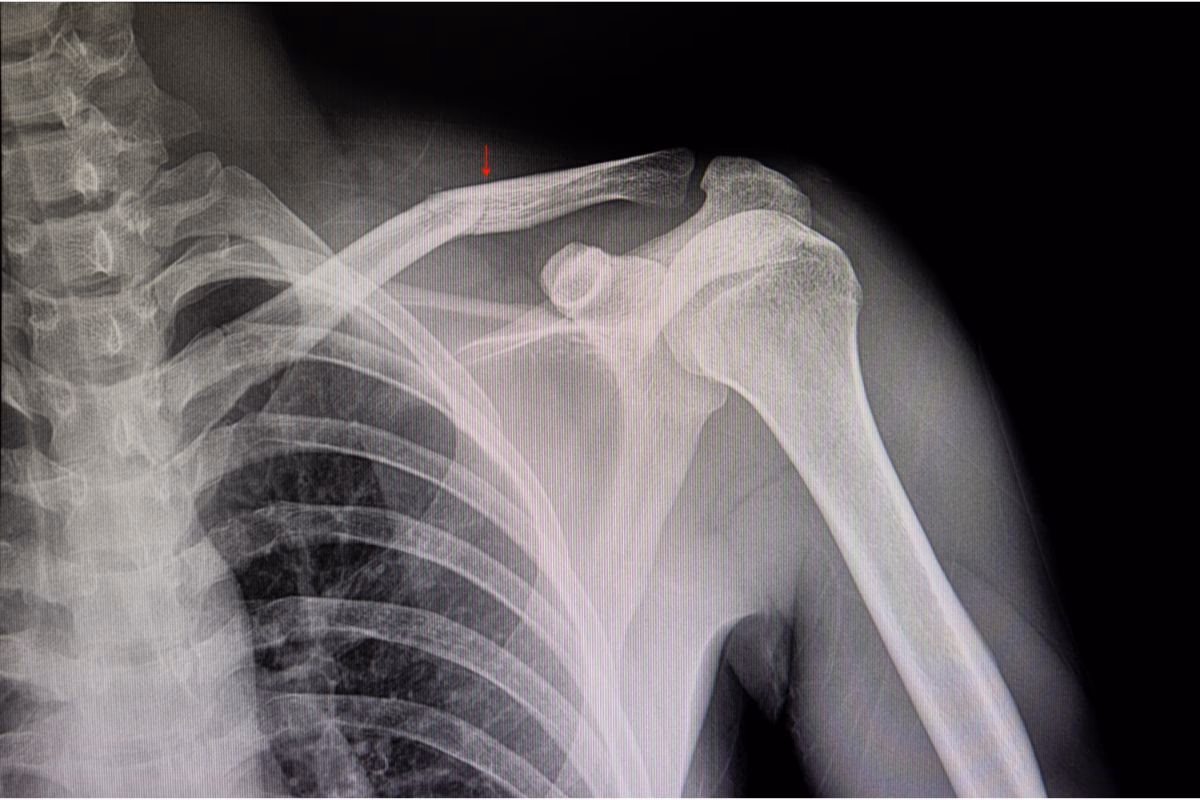

Para confirmar el diagnóstico y determinar la ubicación exacta, el tipo y la gravedad de la fractura, se solicitará una radiografía. La radiografía es la herramienta de imagen estándar para visualizar fracturas óseas y es fundamental para decidir el plan de tratamiento adecuado. En algunos casos, si hay sospecha de daño a los tejidos blandos circundantes o si la fractura es compleja, se podrían considerar otras pruebas de imagen, aunque la radiografía es típicamente suficiente.